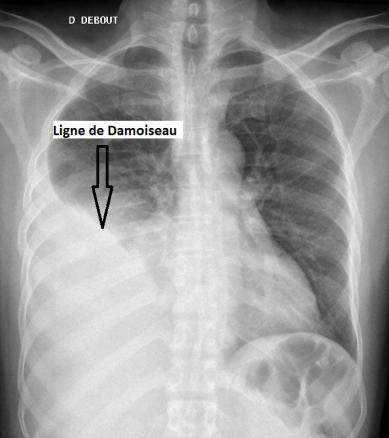

Épanchement pleural droit

Radiographie thoracique